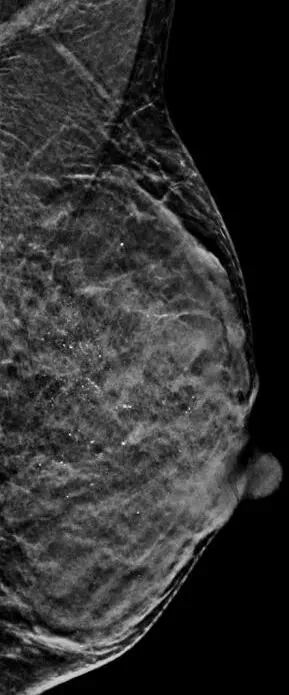

2021年6月9日,在上海交通大学医学院附属新华医院放射科汪登斌主任率领的乳腺影像团队成功开展了一例门诊患者乳腺微钙化的TOMO(断层)模式引导下乳腺3D立体定位活检(Tomosynthesis-guided stereotactic biopsy),国内鲜有开展,在上海尚属首例。该技术创伤小,定位准确,简便快捷,辐射剂量低,是一项安全、高效的影像学定位下微创活检技术。 3D数字乳腺断层成像立体定位活检装置 患者为39岁女性,近期乳腺X线摄影(俗称钼靶)体检发现左乳可疑微小钙化,乳腺超声及MRI检查均未见明确可疑恶性病变,患者迫切希望能够明确诊断,并尽可能采用微创方式。因此,汪登斌主任率领的乳腺团队对该患者病情进行了反复讨论,经与患者协商,决定对乳腺钙化灶实施TOMO(断层)模式引导下乳腺3D立体定位活检。 TOMO引导下乳腺立体定位活检系统 确定旋切刀位于钙化灶正前方进针 首先,技师先为患者拍摄定位片,汪登斌主任选择病灶最集中的层面确定穿刺点,一般系统根据病灶所处坐标的X、Y、Z三轴数据确定是否在安全值范围内,并按病灶深度和安全值,决定选择全槽或半槽,鉴于此例患者病灶位置较浅,汪主任决定活检取材时刀口采用半槽模式。随后消毒、安装旋切针、局麻、进针。通过第二次摄片,确认刀口到达病变区域后即进行旋切。病灶切除后进行最后一次摄影,评估旋切效果。对切除的活检标本进行摄片,并送达病理科。全程仅耗时13分钟。 左乳上部段样分布点状钙化 活检标本摄影显示成簇微小点状钙化 3D数字乳腺断层成像立体定位活检 VS 传统2D乳腺X线摄影定位活检 3D数字乳腺断层成像立体定位功能能够让医生在断层图像上发现隐匿性病变并直接进行定位活检操作,所以此功能能够让临床更准确地对乳腺病灶进行定位与活检; 3D数字乳腺断层成像立体定位功能仅需要一次断层扫描即可完成对病变的定位。相对于传统2D引导,立体定位能够减少拍摄次数,能够有效的提高技师的工作效率,提升整体定位活检等操作的效率,改善工作流程。 由于拍摄次数的减少,整体辐射剂量可降低30%—60%,提供了更为安全的定位活检操作。 汪登斌 主任医师 教授 科主任 博士生导师 研究方向: 乳腺、腹部影像学诊断;分子影像学及靶向探针研究 特需门诊: 周一、周四上午 详细介绍: 上海交通大学医学院附属新华医院放射科学科带头人、放射科主任、医学影像学教研室主任。国家住院医师规范化培训基地主任、上海市专科医师规范化培训基地主任。上海市卫生系统优秀学科带头人。在乳腺、腹部影像诊断方面具有较深的造诣。学术兼职包括中国妇幼保健协会放射医学专业委员会主任委员,中华医学会放射学分会乳腺专委会副主任委员,中国医师协会放射医师分会委员兼影像人工智能专委会副主任委员,中国研究型医院学会肿瘤影像专业委员会常务委员兼乳腺组组长,上海市医学会放射学分会副主任委员兼乳腺组、儿科组、分子影像组顾问,上海市中西医结合学会医学影像学专业委员会副主任委员,上海健康医学院教育委员会委员,上海市卫生系统高级专业技术职务评审评委,国家科技部重点研发计划等评审专家,担任7本核心期刊的常务编委或编委,以及北美放射学会(RSNA)、美国放射学会(ARRS)、欧洲放射学会(ESR)通讯会员。在国内较早开展乳腺病灶的影像学定位并独立完成活检(国内其他医院一般均由外科医师操作),显著提高了早期乳腺癌的诊断率。同时还是我国“乳腺MRI检查共识”执笔人;先后主持国家级及省部级课题近20项,获得包括上海市卫生系统优秀学科带头人培养计划在内的人才计划7项,发表学术论文150余篇,其中SCI论文50余篇。领衔完成科研成果:“乳腺疾病影像学系列研究”,作为第一完成人获得“上海市科技进步奖三等奖”及“上海医学科技奖三等奖”各1项;作为主要完成人获得“国家科技进步二等奖” 等奖项多项。曾受邀在2016年韩国放射学年会,2019年中日韩乳腺影像会议及2019年RSNA上做演讲,阐述我国乳腺癌筛查、诊疗诊断及乳腺影像学发展状况等,受到国际同行的肯定。 上海交通大学医学院附属新华医院乳腺外科 Department of Breast Surgery,Xinhua Hospital 上海交通大学医学院附属新华医院乳腺外科是一个集乳腺疾病早期诊断、精准手术、规范综合治疗、教学、科研和预防为一体的专业学科,是国家级普通外科临床重点专科的重要组成部分,也是上海交通大学乳腺癌临床医学中心组成单位,承担本科、硕士、博士研究生和规范化住院医师的培训,是新华医院重点发展的学科。本专业所有医生均具有研究生以上学历,拥有高级职称5名,主治医师2名,住院医师5名,硕士3名,博士9名,博士后1名。硕士研究生导师2名,博士研究生导师1名,博士后指导教师1名。 新华医院乳腺外科目前是国内著名的乳腺外科手术学培训中心,是中国乳房重建外科联盟主席单位、中国乳腺外科微创治疗与腔镜手术联盟副主席单位、最后一公里·精准乳腺整复万名医师培训计划负责单位、剑在弦上·规范化乳腺外科手术学培训全国巡讲项目负责单位、母乳喂养指导师师资培训全国示范中心、与美丽同行志愿者联盟主席单位、中国妇女发展基金会、与美丽同行·女性健康关爱计划负责单位。 早期诊断:在乳腺肿瘤的早期诊断和精准定位方面居于国内领先水平,拥有目前国内辐射最低的乳腺X线数字摄片系统和精度1mm的计算机定位系统。是华东地区唯一能同时开展乳腺微小肿瘤超声、X线和磁共振钩针定位和微创旋切的单位。 外科手术:在乳腺肿瘤功能性美学重建手术和规范化综合治疗上,积累了鲜明的学术优势,乳腺癌保乳和I期重建比例大于60%,居于国际同步水平,科室成员在国内60多个学术委员会兼职。我们团队在根治肿瘤的前提下,强调保护乳房功能的完整,注重人文、心理学和美学的融合,在乳腺外科手术学上进行了系统的创新,尤其是在保留感觉神经的功能性腋淋巴结清除术、腋窝无痕技术前哨淋巴结示踪活检手术、乳房表面无痕的乳腺癌保乳整复外科手术、中央区乳腺癌的保乳修复、避免术后乳房外形的塌陷畸形、合并乳腺肿瘤的乳头内陷的畸形纠正、保留乳腺手术后哺乳功能等方面处于国内领先水平,形成了具有“精准·精心·精美”特征的“新华模式”,受邀在国内200多个会议主题演讲,被国内同道广泛认可和借鉴,享有“精准新华·精美乳房”的社会盛誉。 腔镜微创手术:目前男性乳房发育从男性的青春期到老年期有较高的发生率。主要原因有青春期的性激素紊乱,药物的副作用导致雄激素降低,肝功能降低造成激素代谢异常等等。男性发育的乳腺组织及周围脂肪,在体型外观上呈现女性化表现,对男性的自信心造成负面影响外。此外,增生的腺体同时存在癌变的风险。我科在上海地区首先采用腔镜微创及溶脂技术,通过隐蔽切口,重塑正常的男性胸部,帮助男性提升自信心及预防癌变风险。 国际化同步药物治疗:依据循证医学和国际乳腺癌临床实践指南与共识,实现国际同步的规范化、个体化的化疗、内分泌和靶向药物等综合治疗。在局部晚期乳腺癌的术前新辅助化疗和复发转移性乳腺癌的综合治疗方面也积累了丰富的经验。近年在乳腺炎症性疾病,特别是哺乳指导、急性乳腺炎、乳腺脓肿和非哺乳期慢性乳腺炎症性疾病的非手术治疗上积累了越来越多的经验。